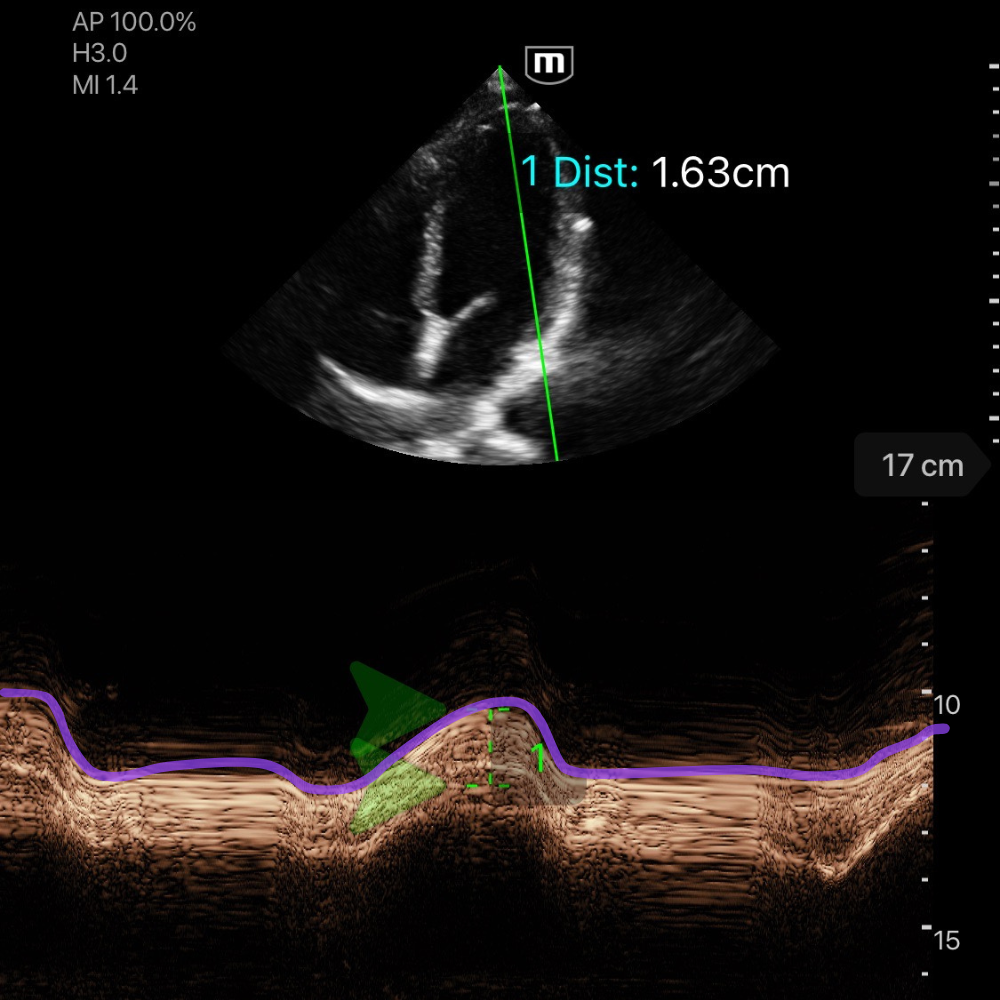

🧮 Calcul MAPSE

Le MAPSE (Mitral Annular Plane Systolic Excursion) mesure le déplacement systolique de l’anneau mitral en mode M.

Le MAPSE est proportionnel à la FEVG : plus le déplacement systolique de l’anneau mitral est faible, plus la fonction systolique du VG est réduite.

Comment mesurer le MAPSE

-

Vue apicale 4 cavités.

Placez le mode M sur l’anneau mitral latéral, ou médial (séptal).

Mesurez la hauteur de l'onde correspondante au mouvement systolique vertical, entre la base de la ligne et le pic (cf. photo ci-dessous, ligne violet).

Interprétation

MAPSE < 8 mm → altération significative de la FEVG

MAPSE 8–10 mm → fonction modérément diminuée

MAPSE > 10 mm → fonction systolique conservée

![]()